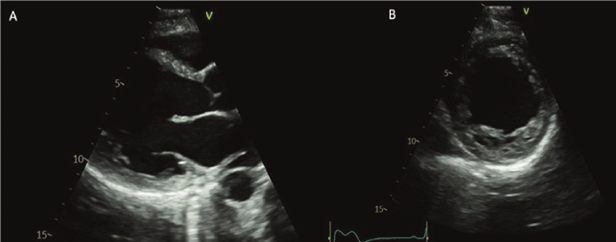

Los controles con ecocardiograma evidenciaban VI dilatado. Disquinesia septal e hipocontractilidad global.

FEVI 40-41%, AI moderadamente dilatada. Insuficiencia mitral leve. Insuficiencia tricuspídea leve con presión sistólica de la arteria pulmonar de 24 mmHg. Sin otros cambios con respecto al ecocardiograma previo al embarazo (figuras 1 y 2).

Figura 1. Ecocardiograma transtorácico. A-B: enfoque paraesternal eje largo y corto respectivamente que evidencia un ventrículo izquierdo moderadamente dilatado con pérdida de su geometría (remodelado esférico).